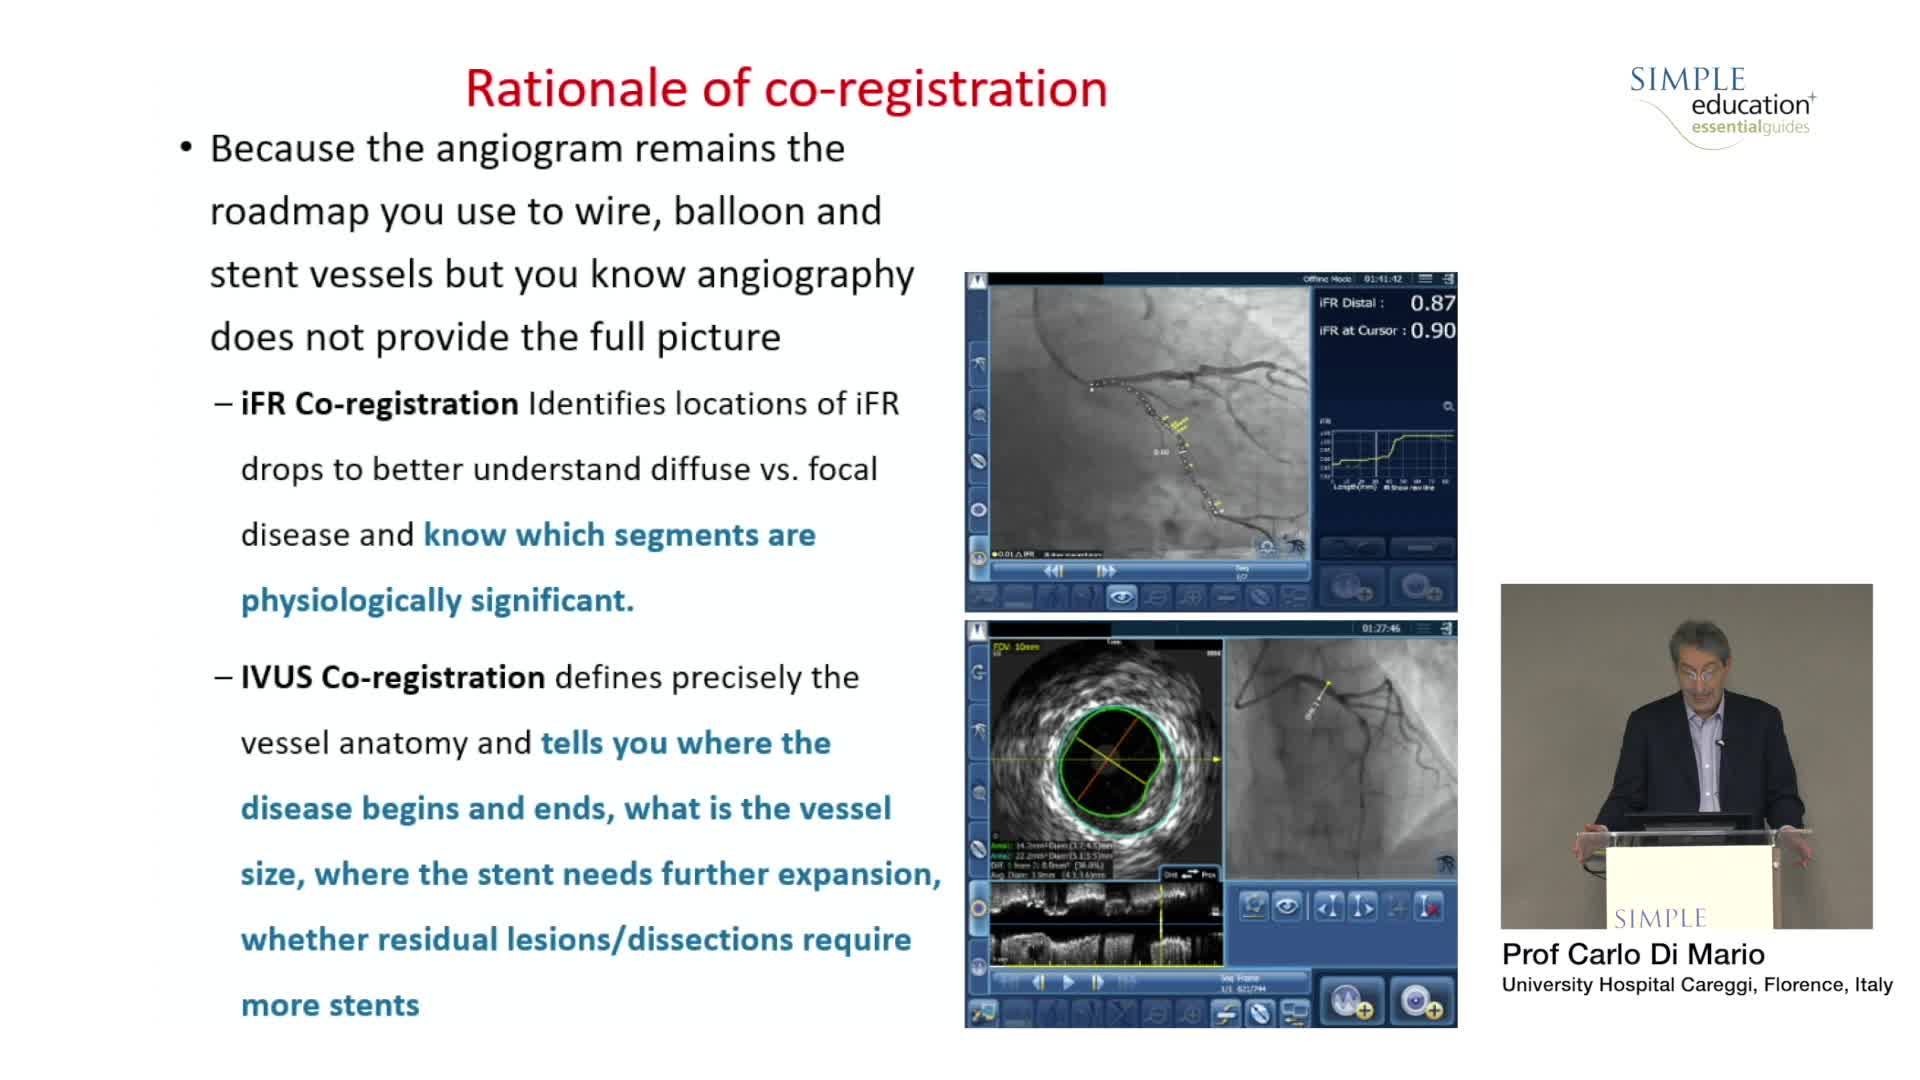

Understanding how SyncVision differs from other co-registration based technologies - Dr Justin Davies

How to perform good co-registration measurements using iFR and IVUS - Prof Carlo Di Mario

Using SyncVision Co-registration to distinguish between focal and diffuse coronary disease. - Prof Giuseppe Tarantini